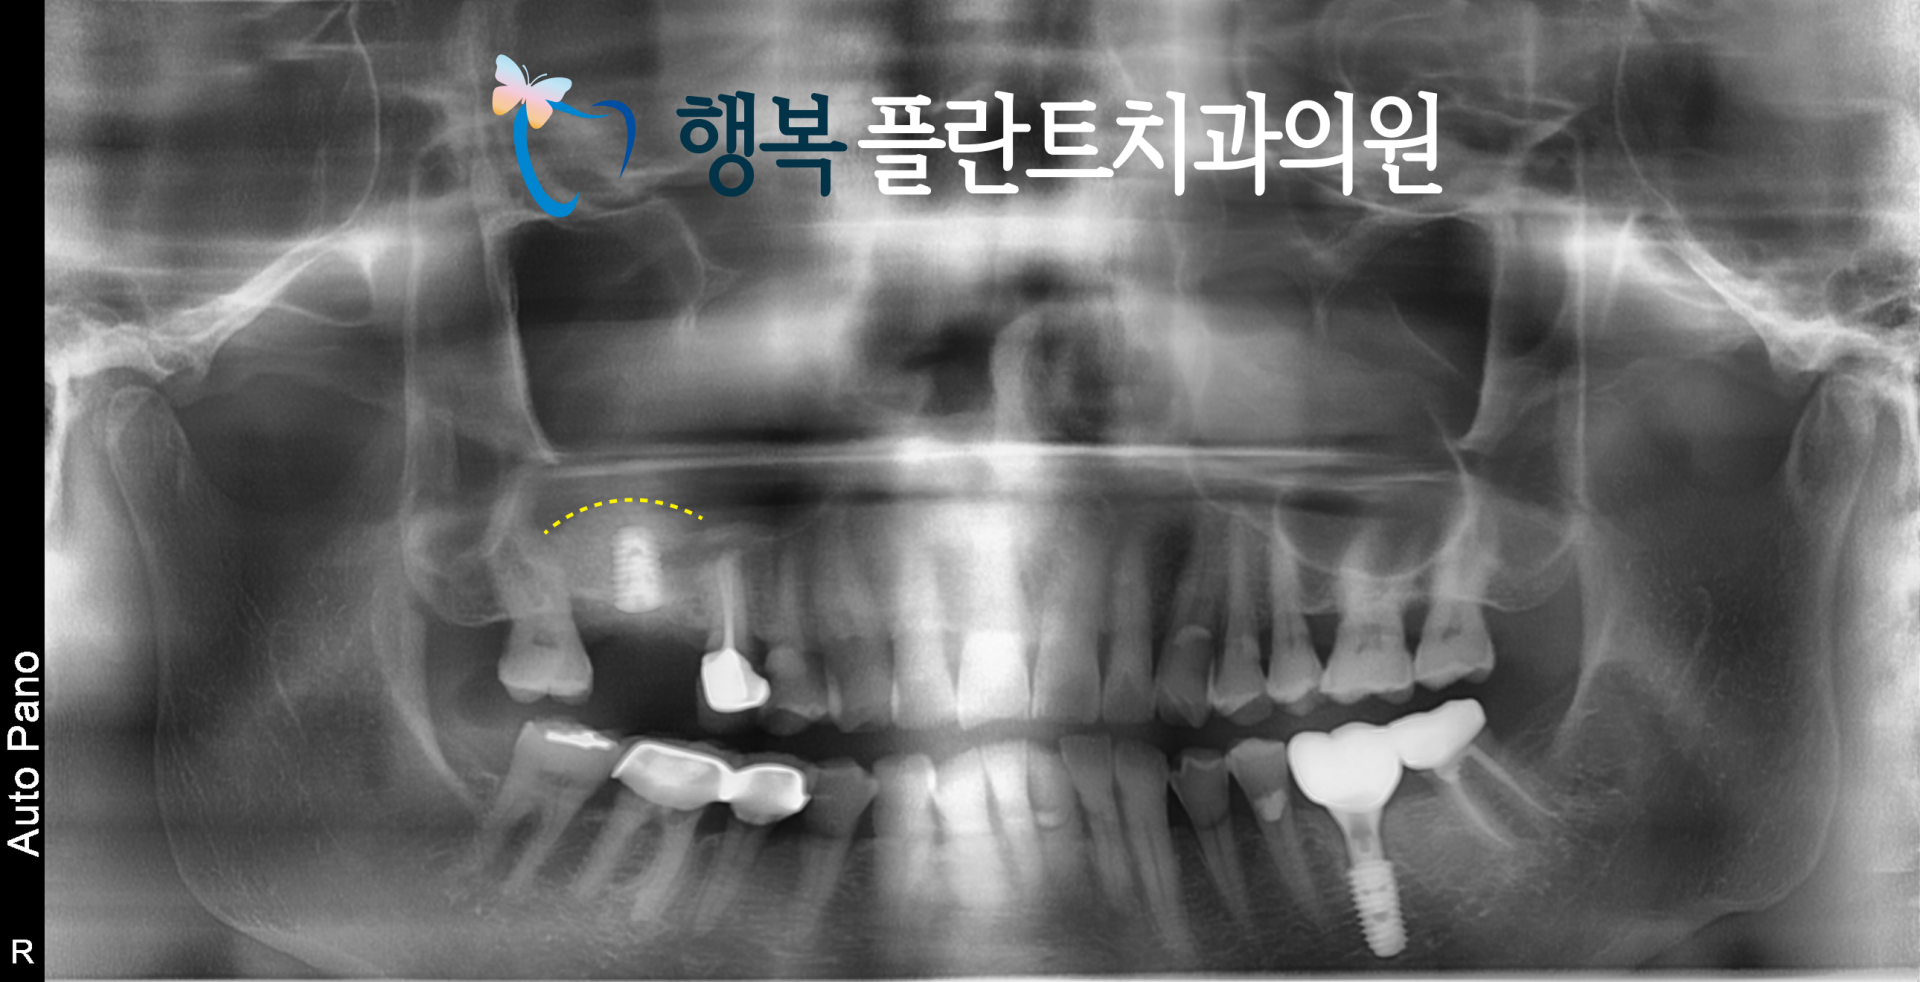

엑스레이를 통해 보면 남아있는 잇몸뼈가 많지 않은 것을 확인할 수 있는데요.

위 엑스레이 사진처럼 발치 후 보존술로 기반을 만들고, 충분한 치유 기간을 거친 뒤

필요한 시점에 맞춰 수압 거상을 통해 상악동 거상술을 시행함으로써 보다 안정적으로 임플란트를 식립할 수 있었는데요.

그렇게 3개월간 치유를 기다린 뒤 다시 CT를 확인해 보니 발치와 부위의 회복은 안정적으로 이루어지고 있었지만

상악동의 영향으로 인해 임플란트를 식립하기에는 여전히 수직적인 골 높이가 다소 부족한 상태였습니다.